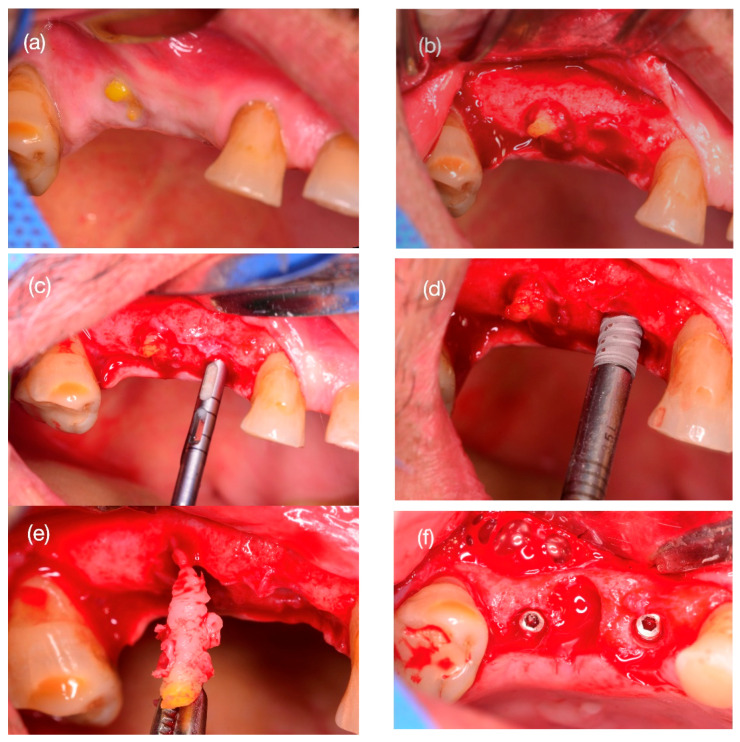

背景与临床意义:通过电喷雾技术对聚己内酯(PCL)三维打印、聚己内酯-嵌段聚乙二醇(PCL- peg)共聚物涂层增强的定制可吸收支架进行放射学和组织学分析,描述其牙槽嵴保存的有效性。病例介绍:一名62岁男性,14号和15号牙齿垂直根骨折。利用锥形束CT (cone beam CT, CBCT)图像,根据支架根的形状设计支架根的复制品,并通过电喷雾的方法将PCL涂覆在PCL- peg上进行打印。将支架插入牙槽骨,并通过无张力皮瓣关闭维持。六个月后,对手术部位进行CBCT检查,并对种植体安装部位的骨样本进行组织学分析。6个月后,14号牙伤口愈合,临床证实无不良反应及并发症。骨样本的组织学分析显示新骨形成具有板层结构、哈弗氏管结构和骨细胞间隙。然而,15号牙的支架是暴露的,没有骨整合,并且被膜组织覆盖。组织学上,样本显示组织与松弛的结缔组织相容,并伴有混合炎症浸润。在第14颗牙齿中,种植体的插入扭矩为bb0 35 Ncm,安装3个月后恢复。结论:三维打印PCL支架具有再生生命骨和功能骨的能力,具有骨整合能力,可用于种植牙的上颌骨再生和口腔康复。一例不充分的支架骨整合伴随着松散的结缔组织形成。

Background and Clinical Significance: To describe the effectiveness of alveolar ridge preservation under the radiological and histological analysis of a customized resorbable scaffold three-dimensionally printed with polycaprolactone (PCL) reinforced with a coating of a copolymer of polycaprolactone-block-polyethylene glycol (PCL-PEG) by electrospray. Case Presentation: A 62-year-old male with vertical root fractures of teeth #14 and #15. From the cone beam CT (CBCT) image, the scaffold root replicas were designed with the shape of the roots and printed with PCL coated with PCL-PEG by electrospray. The scaffold was inserted into the alveolar bone and maintained with a tension-free flap closure. After six months, a CBCT of the surgical site and histological analysis of a bone sample at the dental implant installation site were performed. After 6 months, the wound in tooth #14 was closed, clinically proving no adverse reaction or complications. The histological analysis of the bone sample showed new bone formation with lamellar structure, Haversian canal structure, and osteocyte spaces. However, the scaffold in tooth #15 was exposed and not osseointegrated, and it was covered with membranous tissue. Histologically, the sample showed tissue compatible with lax connective tissue with mixed inflammatory infiltrate. In tooth #14, the dental implant presented an insertion torque >35 Ncm and was rehabilitated three months after its installation. Conclusions: Three-dimensional printed PCL scaffolds showed the ability to regenerate vital and functional bone with osseointegration capability for maxillary bone regeneration and oral rehabilitation based on dental implants. A case of inadequate scaffold osseointegration accompanied by lax connective tissue formation is shown.